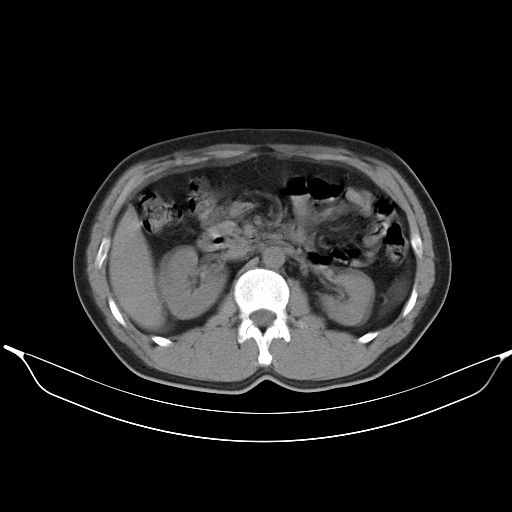

标题: CT25490:男,40岁,体检发现;无其它不适。 [打印本页]

标题: CT25490:男,40岁,体检发现;无其它不适。

考虑:1、过各敏性肺炎可能性大,建议定期复查。

2、轻度脂肪肝。

转移性肺肿瘤不排除,建议结合相关检查考虑

考虑右下肺周围性肺癌并肺内多发转移,纵隔淋巴结转移!

支持 !考虑右下肺周围性肺癌并肺内多发转移,纵隔淋巴结转移,(气管前腔静脉后,隆突下,主动脉弓下都有了)

1、均为转移,原发灶不在肺内。2、肺癌肺转移。